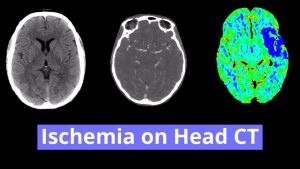

- Posterior Inferior Cerebellar Artery (PICA) Infarct